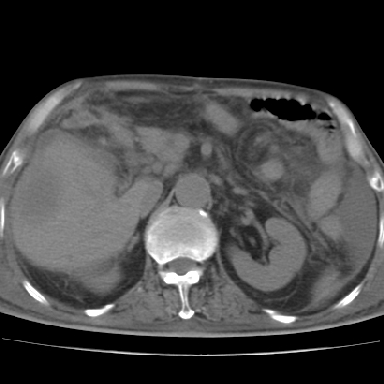

以下是引用chry3在2006-12-4 21:05:00的发言:[br]应该往上扫几层,我考虑膈下脓肿。[br]大家考虑:胃部手术怎会造成肝内脓肿,隔下脓肿到是会造成的

以下是引用qian在2006-12-4 19:11:00的发言:[br]胸腔和腹腔内均见有液性影,肝上极包膜下有一较大椭圆形低密度影,密度均匀,边缘清晰,结合病史考虑术后肝脓肿并胸腹腔积液。

以下是引用dyqct在2006-12-4 19:54:00的发言:[br]考虑:1、肝包膜下脓肿;[br] 2、少量腹水;[br] 3、右侧少量胸膜腔积液。